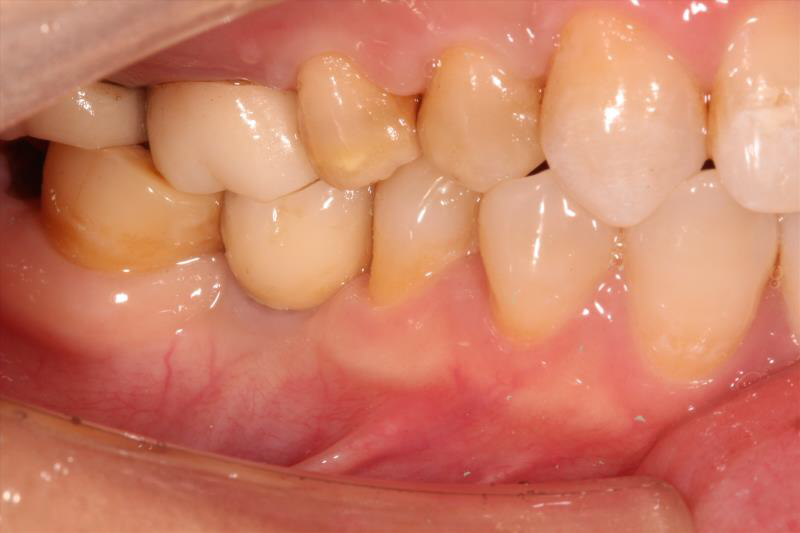

患者中年女性,右上6外院根管治疗多年,近期牙龈红肿,咀嚼疼痛,X线检查见根尖区大面积低密度影响,怀疑有遗漏的根管没有清理,用铒激光无损拆掉牙冠后进行根管再治疗,找到了遗漏的MB2,妥善的根管治疗完成后,重新戴上之前拆掉的牙冠,即解决了疼痛又为患者节省了一笔费用。